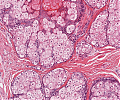

A82 Appendix-Karzinoid

Große, nestartige Verbände neuroendokriner Tumorzellen

A82 Appendix-Karzinoid

Tumorzellnester und diffuse Infiltration der neuroendokrinen Tumorzellen

Appendixkarzinoid

Erkennbar sind isomorphe Tumorzellnester

Appendixkarzinoid

Neuroendokriner Tumor mit nestartigen, trabekulären Formationen isomorpher Tumorzellen